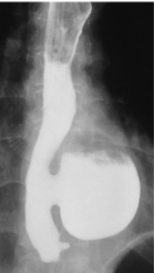

Impaired relaxation & spasm of Cricopharyngeal muscle after swallowing → Pharyngoesophageal Diverticulum (Zenker)

Zenker → Dysphagia & sense of a lump in the throat; food trapping leads to regurgitation of food, chronic cough; Halitosis; Infection

Zenker Diverticulum

Epinephric Diverticulum